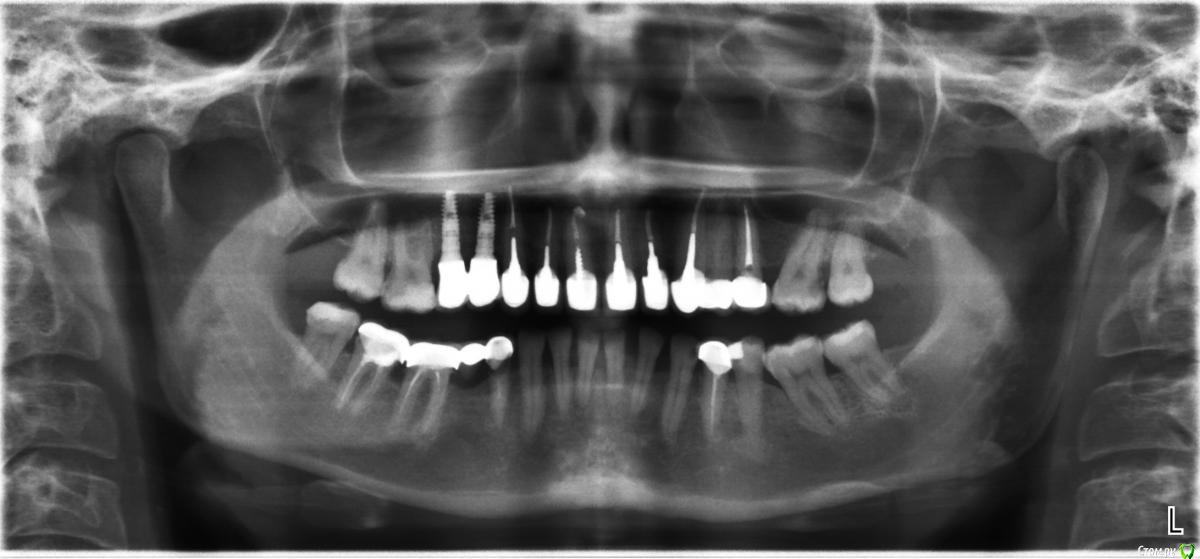

Винкс Опубликовано 25 мая, 2015 Поделиться Опубликовано 25 мая, 2015 Речть идет про правый низ. Сняли мост 4-5-6-7.Приговор: 4 на удаление, потом имплант. 5 - имплант, 7 пролечили.Вопрос стоит про 6. Каналы не удалось распломбировать, там "камень" по словам доктора. Что с ней делать? Оставить так или удалить?Если удалить, то как вы смотрите на мост на двух имплантах.Если это тема не для терапии, то перенесите плз. Дополнительно. Ссылка на комментарий

Alejandro Опубликовано 29 мая, 2015 Поделиться Опубликовано 29 мая, 2015 (изменено) Нет пока повода для паники. Смело инсталируйте имплантаты в области премоляров, если клиники в первом моляре нет и не было. Больше беспокоит карман между 6 и 7. Шестёрка со временем уйдёт, но как и когда никто не скажет. Уйдёт шестёрка - ещё один имплантат. Изменено 29 мая, 2015 пользователем Alejandro Ссылка на комментарий

Винкс Опубликовано 1 июня, 2015 Автор Поделиться Опубликовано 1 июня, 2015 Нет пока повода для паники. Смело инсталируйте имплантаты в области премоляров, если клиники в первом моляре нет и не было. Больше беспокоит карман между 6 и 7. Шестёрка со временем уйдёт, но как и когда никто не скажет. Уйдёт шестёрка - ещё один имплантат.Вот вы мне написали про карман... После ирригатора отдуда кровит постоянно после снятия моста. Я сначала думала, что там ткани не привыкшие к струе, но уже целый месяц прошел. Ссылка на комментарий